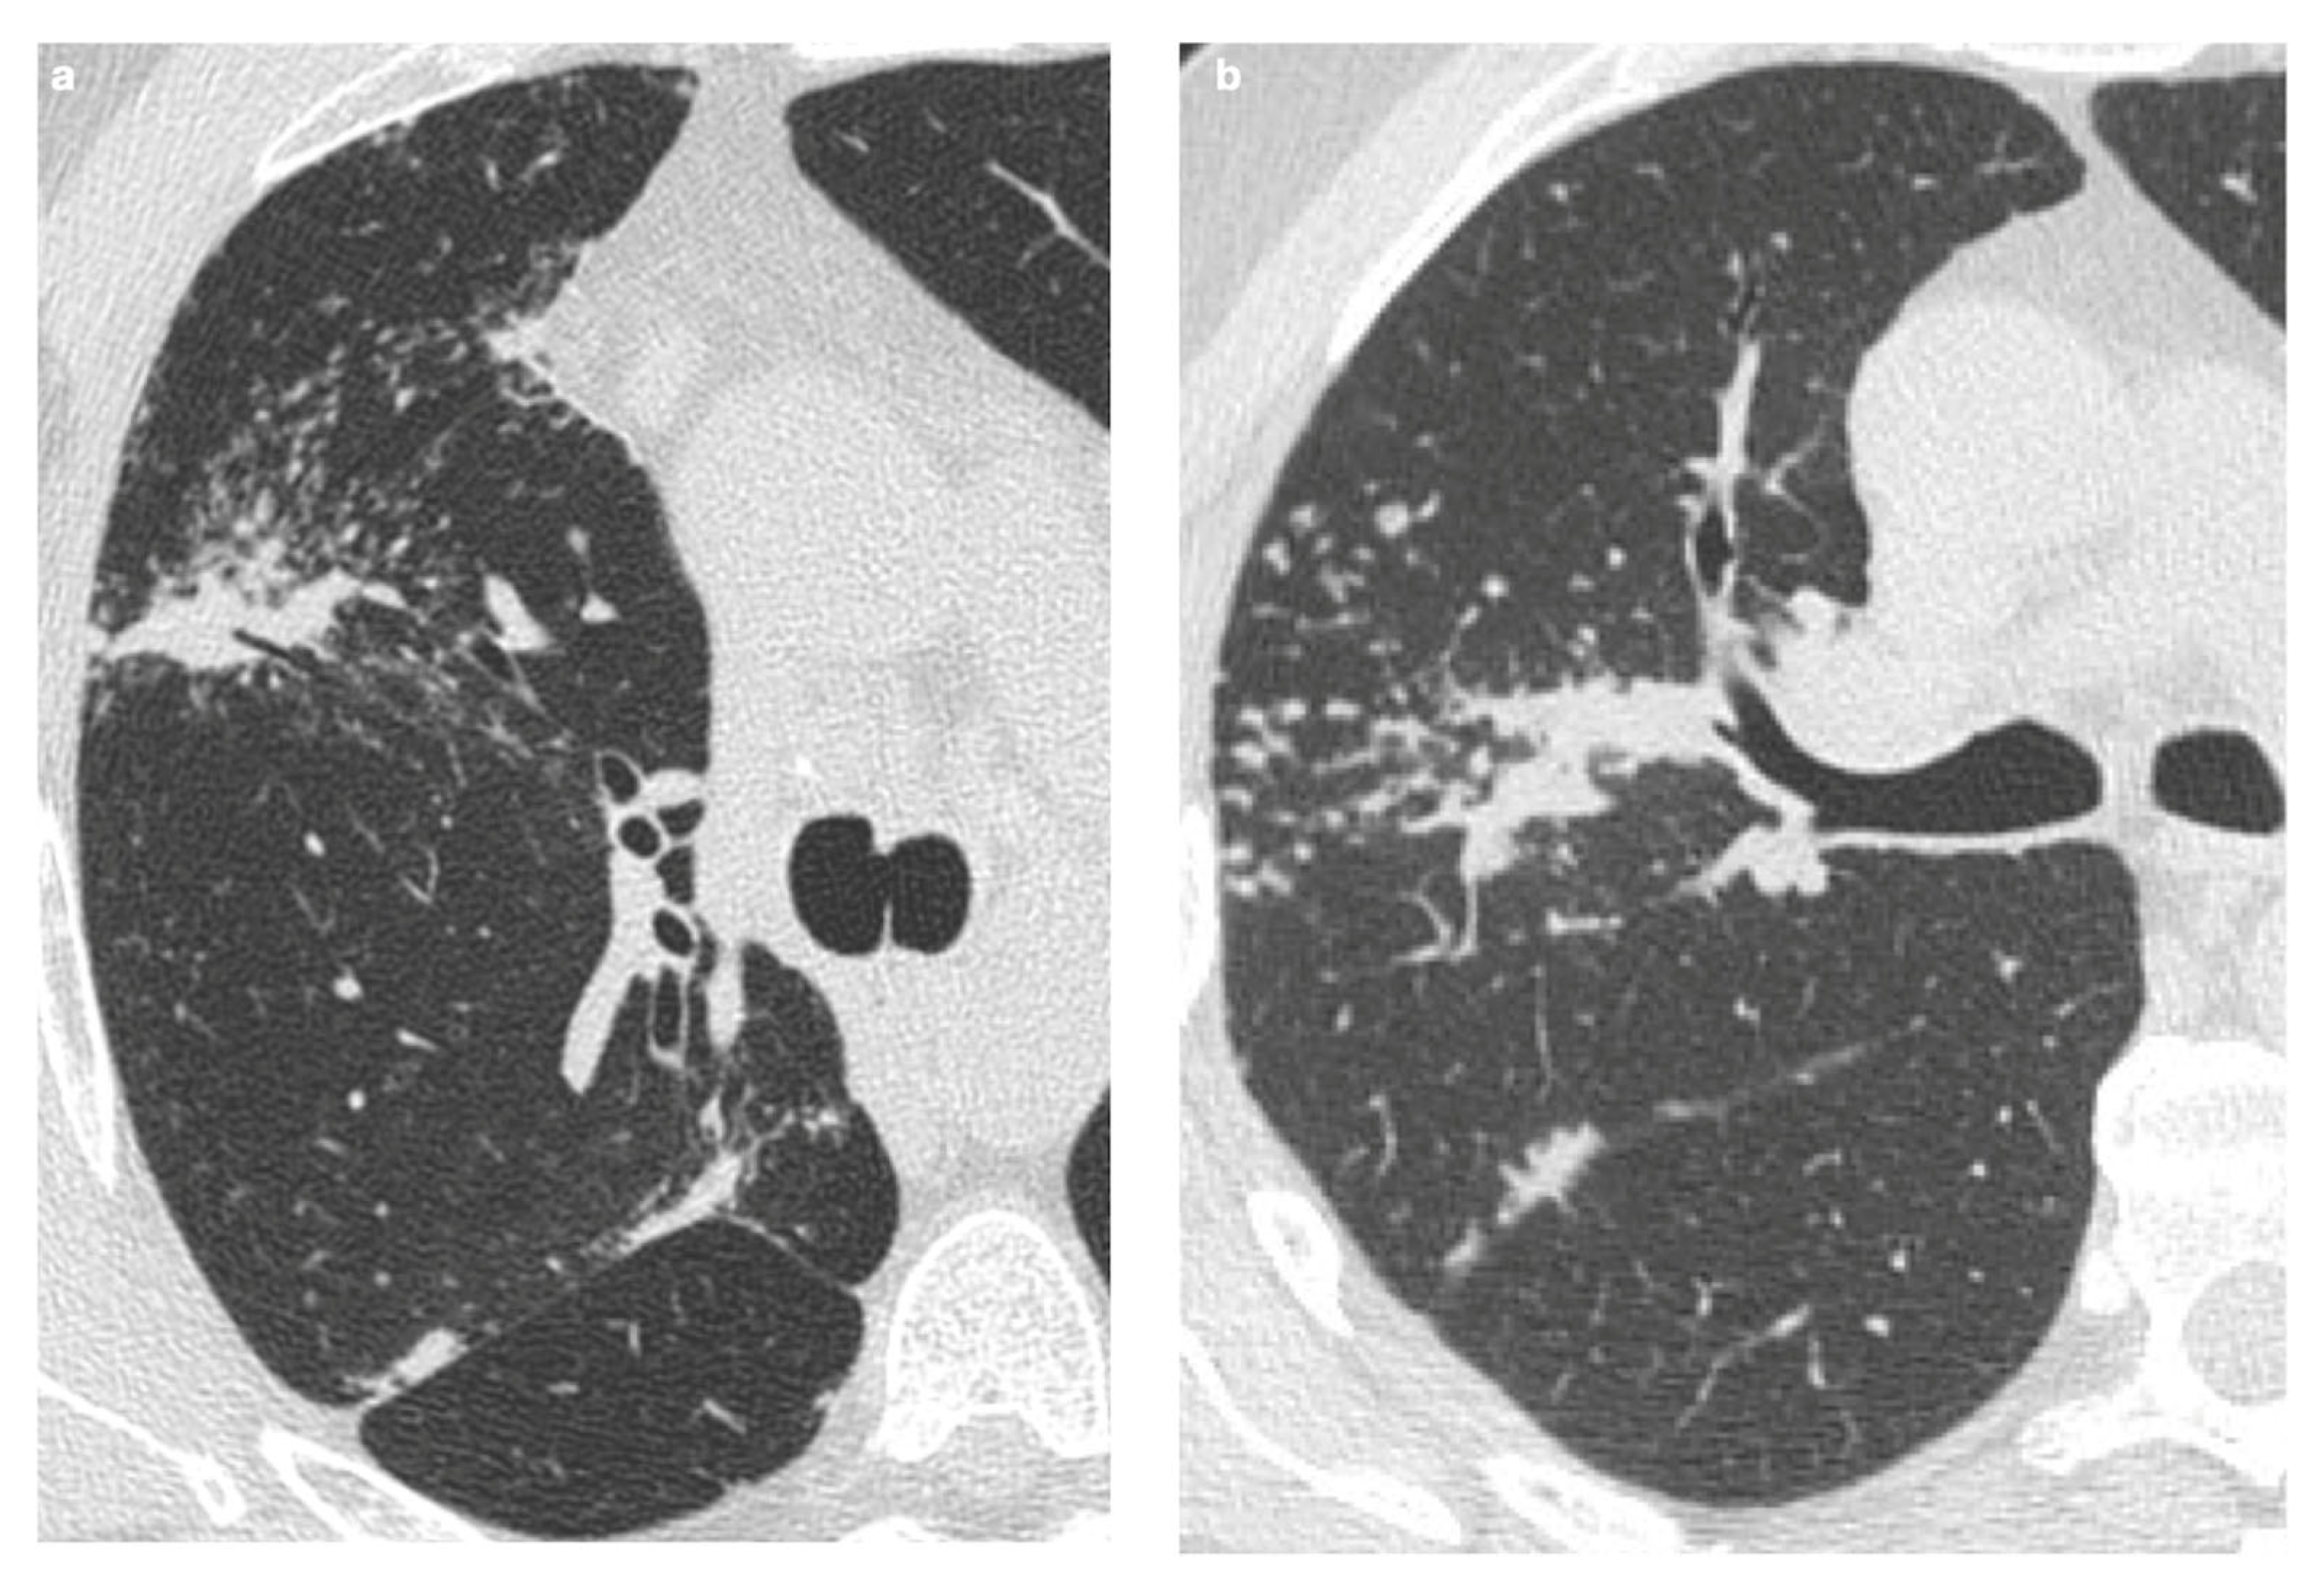

5. Fibrosis

5.1. Progressive Fibrosing Form

| Incidence | Approximately 20% of patients with sarcoidosis |

| Origin | Chronic inflammation, long-lasting disease, or phenotypic susceptibility |

| Alterations | Linear opacities, traction bronchiectasis, architectural distortion |

| Distribution | Predominantly in the upper lobes and peribronchovascular regions |

| Honeycombing | Present in about 10% of patients, typically localized in middle-upper lobes |